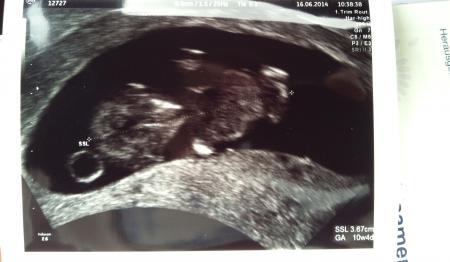

Alles o.k. mit dem Krümelchen... hat geschlagen, es ist größer geworden und mittlerweile 3,67 cm groß.

Die Woche ist auch geblieben, bin nun 10+4 wie berechnet und ET bleibt der 7. Januar.

Und hier das Bild...